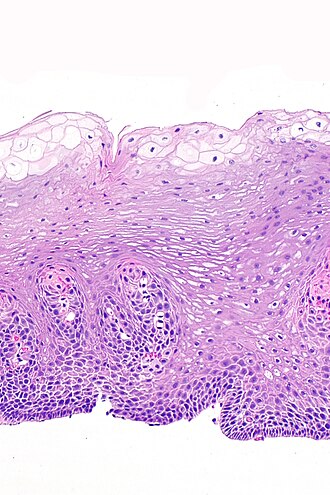

Glycogenic acanthosis of the esophagus. H&E stain. | |

| LM | squamous epithelium with (1) superficial clearing of the cytoplasm, and (2) thickening |

| Stains | PAS +ve, PASD -ve |

- Squamous epithelium with:

- Superficial clearing of the cytoplasm.

- Thickening.

- No significant nuclear atypia.